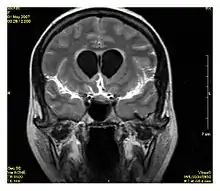

Fluid-attenuated inversion recoveryFLAIRFluid suppression by setting an inversion time that nulls fluidsHigh signal in lacunar infarction, multiple sclerosis (MS) plaques, subarachnoid haemorrhage and meningitis (pictured).[24]